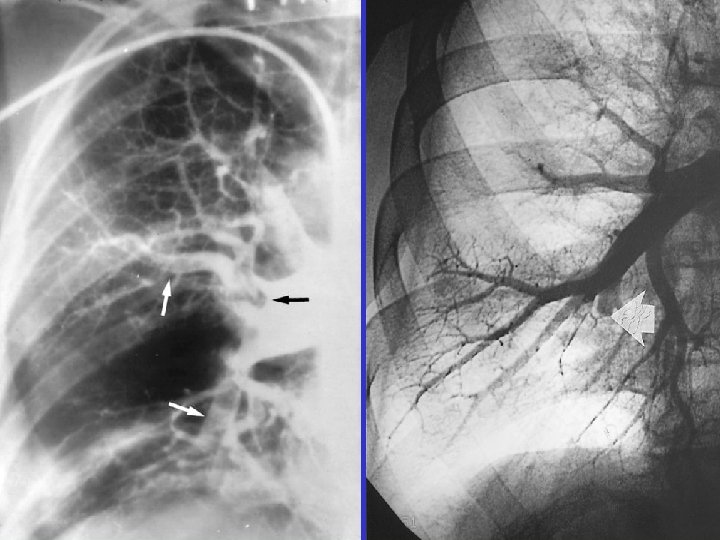

Angiography

Angiography: massive PE Acute: 45/20 mm. Hg Subacute: 85/50 mm. Hg